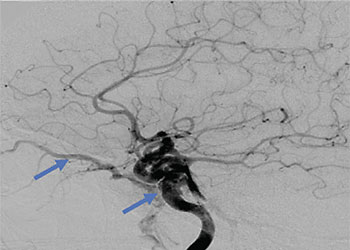

Endovascular:

Carotid Cavernous Fistula (CCF)

Author: Jonathan L. Brisman M.D., F.A.C.S., Read More!